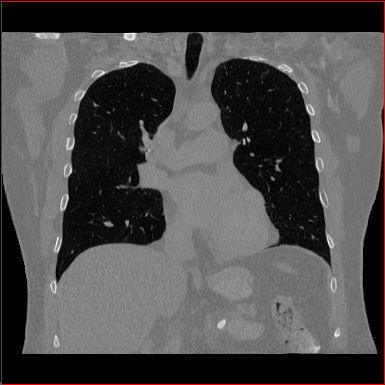

Figure 2: Qualitative comparison across axial (top row), sagittal (middle row), and coronal (bottom row) views. Columns correspond to different methods. MAISI-DDPM and MAISI-v2 in this figure are unconditional synthesis which do not use ControlNet or segmentation maps.

Qualitative Evaluation:

Figure 2 presents representative slices from the axial, sagittal, and coronal planes. GenerateCT (hamamci2024generatect) is a 2D model, so it lacks inter-slice consistency, leading to poor image quality in the sagittal and coronal views. MedSyn (xu2024medsyn) produces noticeably blurry results with mosaic-like artifacts, such as region inside the red box. HA-GAN (sun2022hierarchical) generates visually sharp images but with mosaic-like artifacts, such as region inside the red box. Also, its voxel spacing is not available, which limits its applicability in real-world medical imaging tasks. Moreover, all three methods are restricted to synthesizing small anatomical regions. In contrast, both MAISI and MAISI-v2 are capable of generating high-quality 3D volumes that span larger body regions while preserving fine anatomical details and realistic structure.